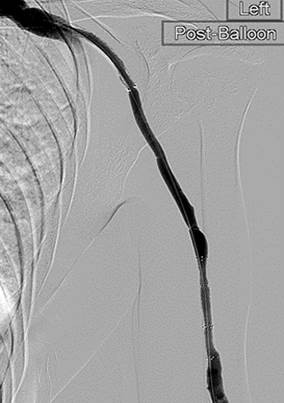

Tras la segunda pasada con el catéter DVX y la angioplastia con balón de la estenosis subyacente. Sin impedancia para el flujo de avance en la FAV.

Una vez que se establezca el flujo de avance y se trate la estenosis, los trombos residuales deberían resolverse.